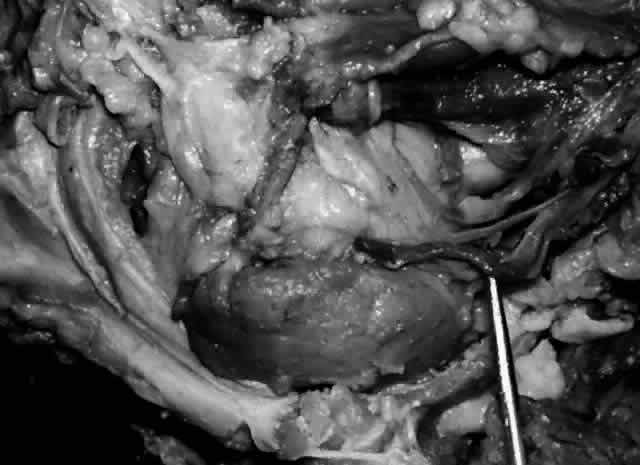

The lacrimal bone is pneumatized by anterior ethmoidal air cells (agger nasi bullae), which occasionally pneumatizes the anterior lacrimal crest. In cases where the lacrimal bone contribution to the lacrimal fossa is dominant (Fig. 27), ethmoidal air cells are more likely to be found in the lacrimal fossa and nasal cavity.19,28 Clinically these air cells separating the upper half of the lacrimal fossa from the nasal cavity, if present, must be opened or removed in order to enter the nasal cavity during dacryocystorhinostomy surgery.

Fig. 27. Ethmoidal air cells extend to the anterior lacrimal crest (arrow), demonstrating a dominant ethmoidal and lacrimal bone contribution to the lacrimal fossa (left orbit).